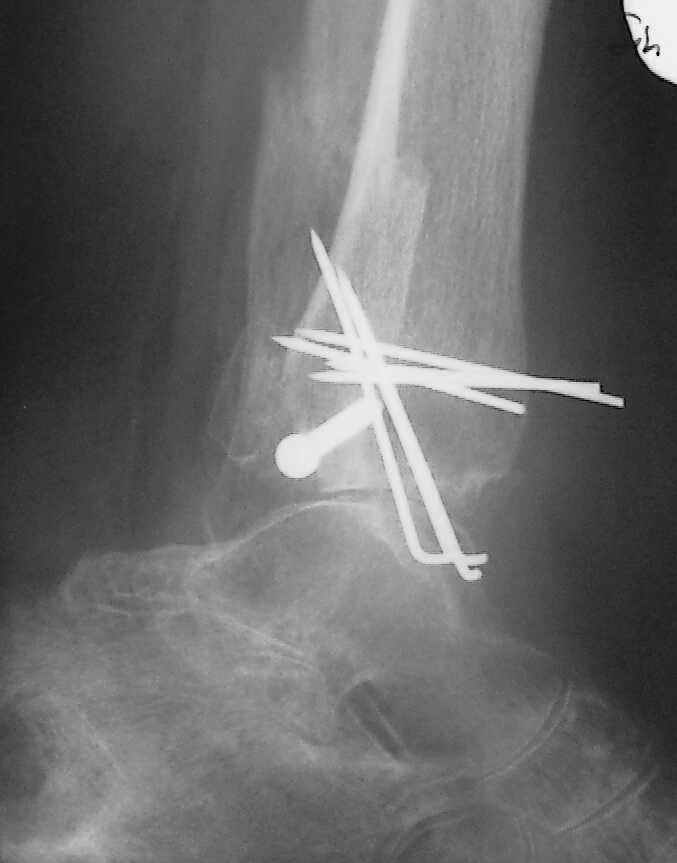

Я бы проблему трактовал как изначально нестабильный и нефункциональный остеосинтез с длительной иммобилизацией у больной с сахарным диабетом, ангиопатией и остеопорозом.

Диагноз я бы поставил: неправильно срастающийся перелом обеих лодыжек и заднего края ББК. Ложный сустав мед. лодыжки? Хронический вялотекущий остеоимиелит голеностопа. Сопутствующий - СД, диабетическая ангиопатия 2.

А почему изначально не сделали хоть по Веберу? В чём смысл 6-ти скусанных спиц? И для чего ввинтили несоответствующий методике шуруп в нижнюю треть остеопорозной, практически отсутствующей лодыжки?

Ретроспективно, на Ваш взгляд, что изменилось бы при остеосинтезе более массивными имплантами?(выбор в пользу спиц как раз и был из-за минимального объема оставляемых имплантов) Иммобилизация 7 недель это очень длительно? Результат на 4 RTG - в чем нефункциональность? - согласен, что репозиция заднего края не была достигнута. Какие признаки ложного сустава мед. лодыжки ?